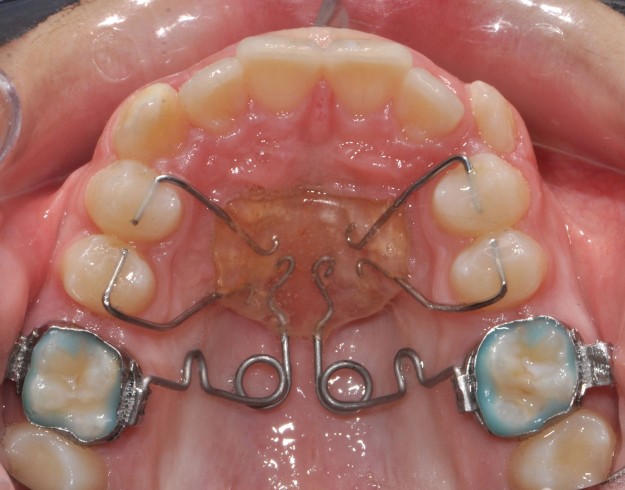

PENDULUM APPLIANCE – PROBLEMS AND POSSIBILITIES IN ITS APPLICATION AT DIFFERENT AGE PERIODS

Статията обсъжда съществували разлика при дистализиране на горни молари, ако пациентите са в различен растежен етап или завършили растежа си, т.е. растящи, млади възрастни и възрастни.